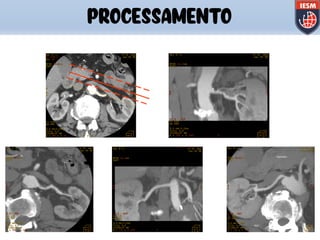

PROCESSAMENTO

120kV/230mA/2.5mmEsp/0.8seg

Volume Rendering MPVR/MIP

120kV/250mA/2.5mmEsp./0.8seg

3D/Angio

MIP